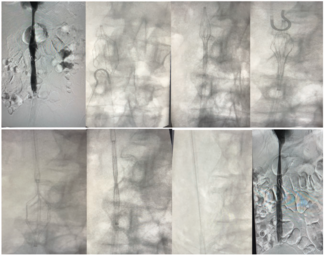

Amir Z. Malik, MD, FACC, FSCAI; Karan Gupta, DO, FACC; Hamza Malik, DO; Maheen Zaidi, MD; Som A. Bailey, DO, MD; Rija Ashfaq, MS; Abdullah Wagley, MS

Here we describe a rare, complex case of IVC filter retrieval and repositioning in a patient with improper filter placement.